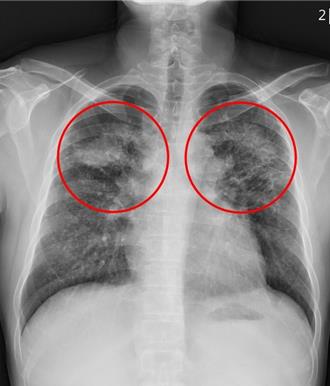

花蓮一名黃先生年輕時曾有近10年的磨石工作經驗,後雖離開該行業,未料44歲自影像檢查中發現肺部有大塊陰影,確診塵肺症導致的肺部纖維化,醫師表示,矽肺症不僅不可逆,還將會持續惡化,沒有特效藥,呼籲從事石材業者工作期間務必使用工業級防護口罩或面罩,「預防勝於治療」。